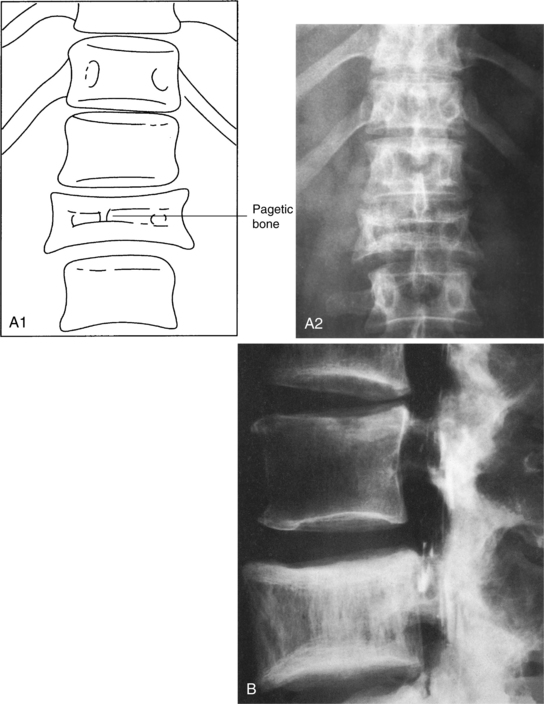

Involvement of the vertebral bodies presents with a picture-frame appearance radiographically as the cortical shell and endplates become greatly exaggerated in comparison to the coarse, cancellous bone portion of the vertebral body (Fig. 24-8). The final stage of the disease is characterized by little cellular activity.

Figure 24-8 A, Clinical radiograph of the spine shows a solitary focus of pagetic bone. A loss of height of the vertebra (compression), some increases in the width of the vertebra, and a typical “picture-frame” appearance are evident. B, Radiograph of the lumbar spine in a 66-year-old male shows enlargement of L4 with coarsening of the trabecular pattern and a margin sclerosis, the so-called picture-framing characteristic of Paget’s disease. (From Bullough P: Orthopaedic pathology, ed 3, London, 1997, Mosby-Wolfe; B, Courtesy Dr. Alex Norman.)